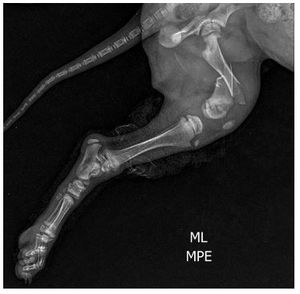

Kiara sofreu um acidente em 05/09 onde acabou fraturando o FÊMUR da perna esquerda e teve uma fissura na perna direita.

o motivo da urgência neste caso é para que a fratura não cicatrize de forma errada, deixando sequelas ou perda da movimentação na perna, além das dores.

as imagens comprovam a necessidade e urgência do caso, contamos com sua colaboração independente do valor, tudo que conseguirmos será bem vindo e ajudará no tratamento dessa pequena que faz parte das nossas vidas.